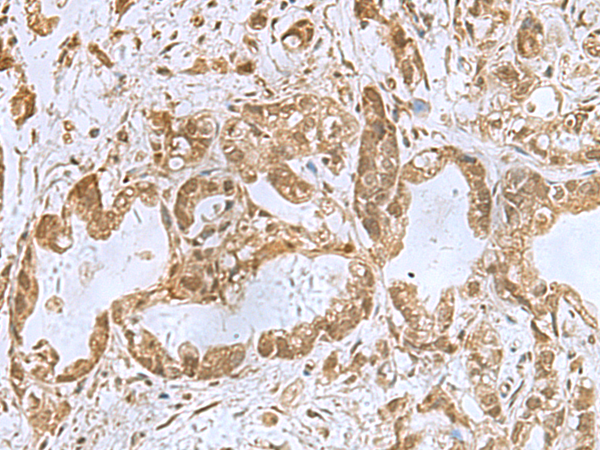

分类: 科研抗体货号: P00649别名: BFLS; BORJ; CENP-31应用: IHC反应种属: Human, Mouse